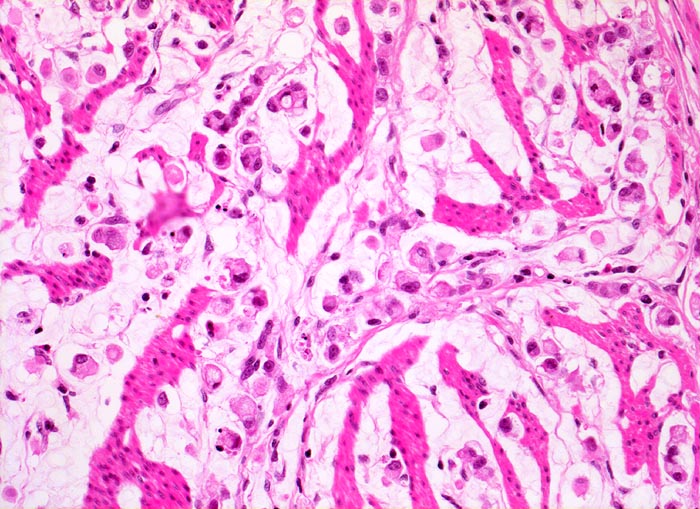

Adenokarzinome können tubuläre, papilläre, muzinöse, siegelringzellige und undifferenzierte Anteile aufweisen, wobei die beiden letzteren besonders aggressive Tumoren darstellen.

• Ein Grossteil des Tumorinfiltrats besteht aus einzeln oder in kleinen Gruppen liegenden Zellen mit intrazytoplasmatischen Schleimvakuolen, die teilweise den Kern verdrängen (Siegelringzellen): diffuser Typ des Magenkarzinoms nach Lauren.

• Nur vereinzelt Drüsenbildung.